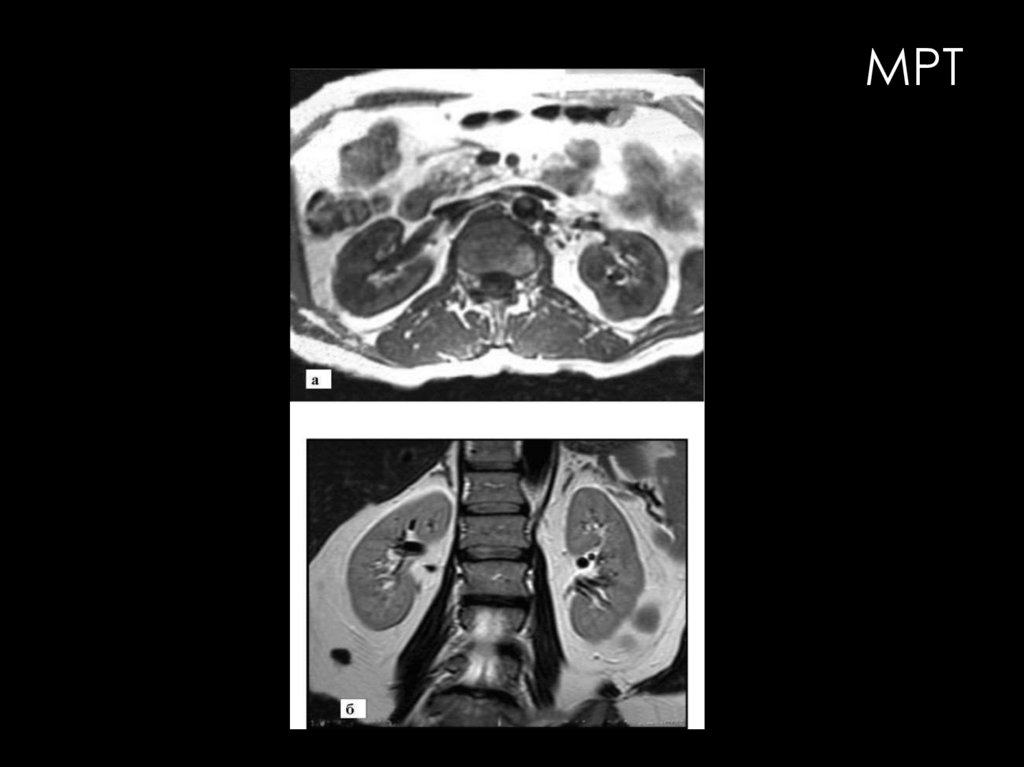

МРТ

Современные высокопольные МР-томографы обладают большими

возможностями визуализации и детальной характеристики всех

мочевых органов. Базовой методикой исследования мочевых

органов является нативная МРТ.

Возможности МРТ в диагностике заболеваний мочевых органов

значительно расширяются при использовании специальных

методик:

•МРТ с контрастным усилением

•МР-ангиография

•перфузионная МРТ.

•магнитно-резонансная

урография (МР-урография)